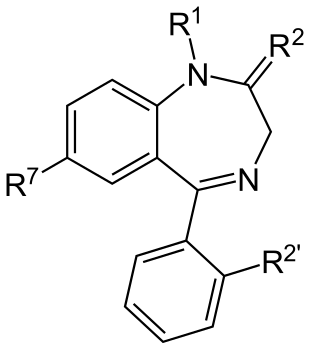

- The therapeutic index of a medication is a comparison of the amount that causes the therapeutic effect to the amount that causes toxic effects. Quantitatively, it is the ratio of the dose required to produce the desired therapeutic effect and the toxic dose. A commonly used measure of therapeutic index is the effective dose of a drug for 50% of the population (ED50) divided by the lethal dose for 50% of the population (LD50).